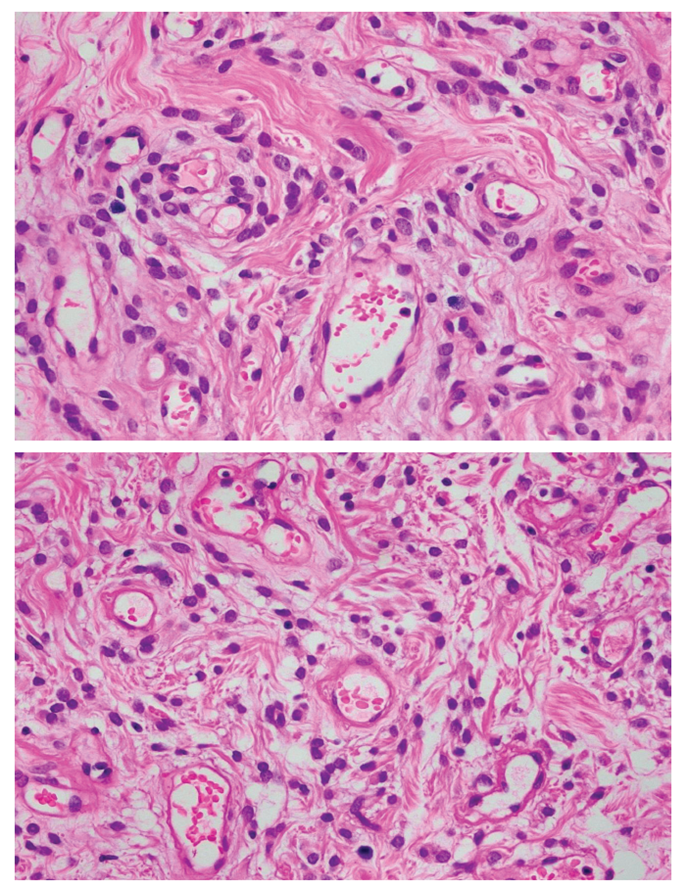

This is a case of a 55-year-old female, surgical menopause for nine years, not on hormone therapy with one year history of a progressively enlarging left vulvar mass, who sought consult and subsequently underwent excision of mass. Microscopic findings showed alternating hypo- and hypercellular areas composed of plump spindle to epithelioid cells distributed in an edematous stroma with varying amount of collagen. Tumor cells have bland chromatin, inconspicuous nucleoli, and absent mitoses. The cells surround small to medium-sized thin-walled, hyalinized vessels found in hypercellular areas. An adipocytic differentiation of more than fifty percent of tumor is observed further classifying this neoplasm as lipomatous angiomyofibroblastoma, making this an even rarer type of benign mesenchymal tumor of the vulva. Immunohistochemistry stains performed showed positive staining for vimentin, smooth muscle actin, BCL-2, ER, PR, and negative staining for desmin which supports the diagnosis. The clinical presentation, operative findings, histopathologic features and the various considerations are discussed. Literature review of vulvar angiomyofibroblastoma is also presented.